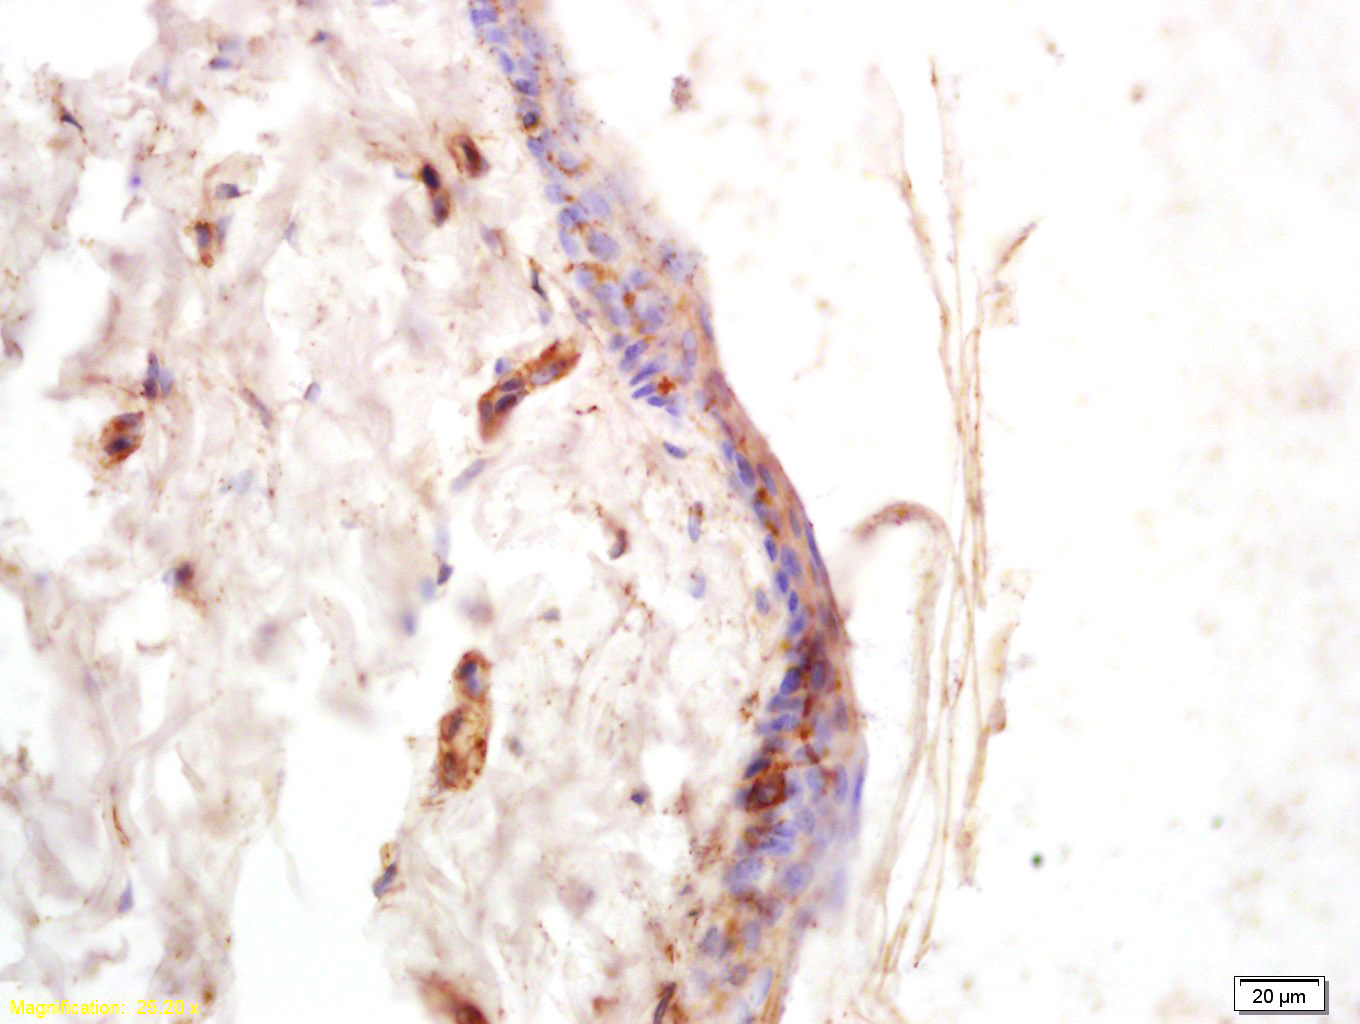

Antigen retrieval: citrate buffer ( 0.01M, pH 6.0 ), Boiling bathing for 15min; Block endogenous peroxidase by 3% Hydrogen peroxide for 30min; Blocking buffer (normal goat serum,C-0005) at 37℃ for 20 min;

Incubation: Anti-COL6A5/Collagen VI alpha 5 Polyclonal Antibody, Unconjugated(bs-11047R) 1:200, overnight at 4°C, followed by conjugation to the secondary antibody(SP-0023) and DAB(C-0010) staining